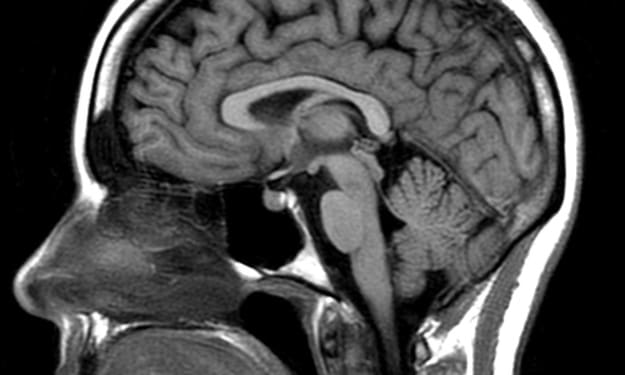

I grew up living with epilepsy, and with this I always resorted to the arts for relaxation and stress relief. My love for music is phenomenal, and my hobby to write stories to share to the world has always been a big dream of mine.

Living with Epilepsy: How It Changed My Life: Part 1

I've come a long way since my first encounter with something I would have to live with for the rest of my life. I was a normal child that enjoyed everything that every child would. Playing outside in the mud, with toys, or even playing with other children that you would meet in the park during the day. I made lots of friends in school and did the best I could to get the highest grades possible. I wanted to grow up and do the best I could in life. I wanted to go to college and earn a degree in my dream job in the field of engineering. I wanted to show my parents the potential I had to achieve whatever I set my mind to.

Two weeks had passed and the results had been sent to a neurologist and my pediatrician to review. The mass that was reported earlier was analyzed further and had a diagnosis. My parents received the call to set up an immediate appointment in order to review the results.